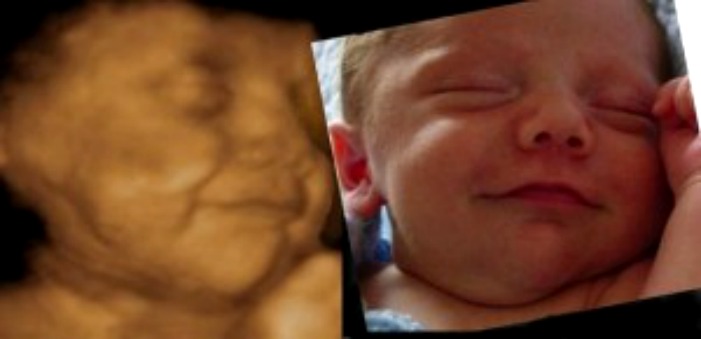

Ultrassom 5d Imagens Mais Nitidas E Detalhadas Do Bebe Revista